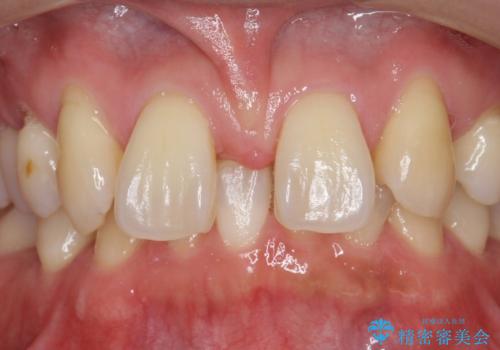

- 前歯部のすきっぱと歯並びが気になるので診て欲しいといらっしゃった方の症例です。

全顎矯正は御希望されなかったため、上顎前歯部のみの部分矯正とオールセラミッククラウンによる補綴を行いました。